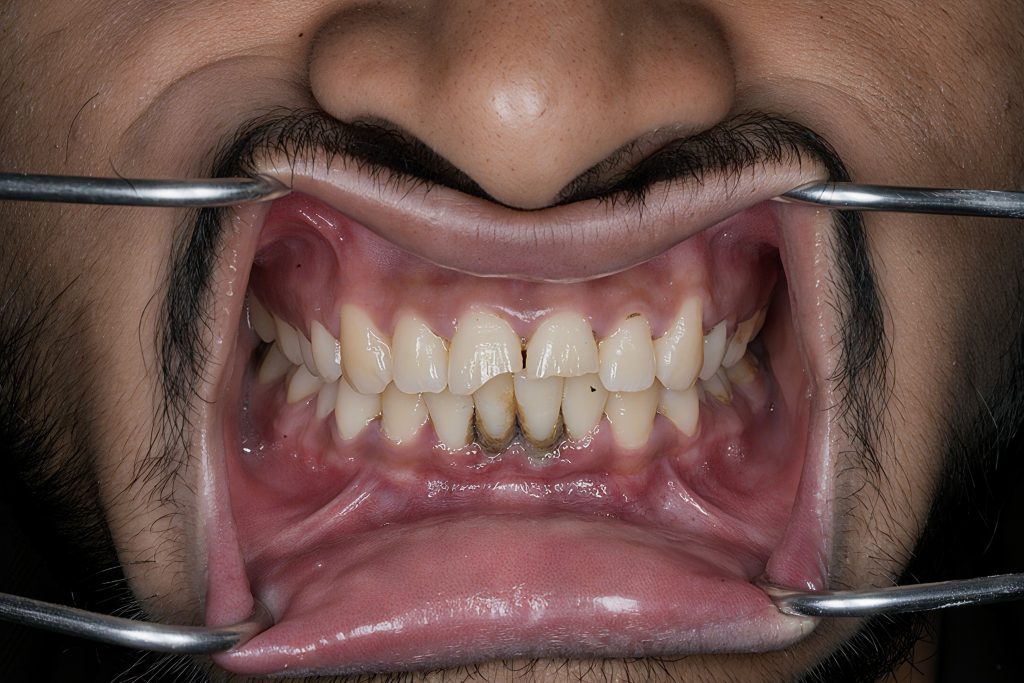

Outcome

- Invisible transition between tooth and composite

- Natural halo effect and depth recreated

- Increased brightness without over-whitening

- Strong adhesive interface thanks to enamel bonding

- Patient extremely satisfied with the natural, clean aesthetic